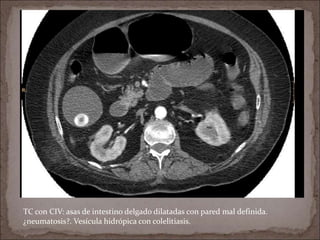

TC con CIV: salida de la AMS calcificada (flecha). Vesícula hidrópica. Asa de

intestino delgado dilatada con pared íntegra.

TC con CIV: asas de intestino delgado dilatadas con pared mal definida.

¿neumatosis?. Vesícula hidrópica con colelitiasis.